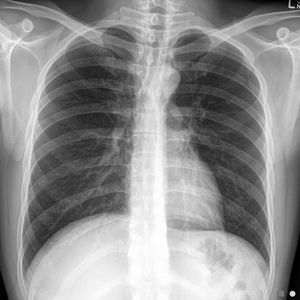

What parts do you see in this CXR?

Is it emphysema

Its emphysema

Lymphoma at lung hilum?